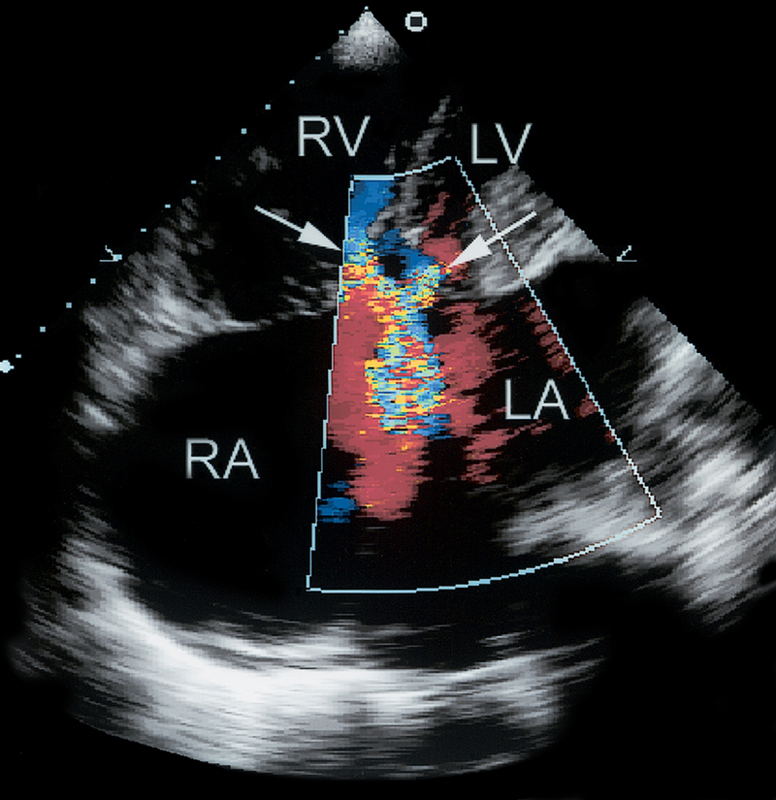

فحوصات تشخيصية لبعض امراض القلب والشرايين التاجية